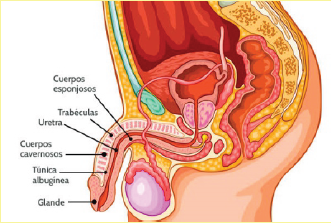

Además, en el colon se localizan terminales nerviosas o puntos reflejos, que inciden en otros sistemas:

- En el sistema nervioso, con el cerebro y la médula espinal como sus piezas principales, que envían señales a otros sistemas del cuerpo para controlar su funcionamiento.

- En el sistema cardíaco, con el corazón y los vasos sanguíneos como protagonistas, que se encargan de transportar sangre con oxígeno y nutrientes hacia todas las células del organismo y de llevar los desechos de éstas hacia los pulmones

- En el sistema endocrino que secreta hormonas, desde distintas glándulas, para que actúen en células específicas que propiciarán un efecto deseado en el organismo.

Los complejos mecanismos por los que actúan estos y otros sistemas, como el digestivo, el respiratorio y el inmunológico, permiten que un cuerpo conserve su estado de salud, gracias al trabajo en equipo ejercido por la unidad funcional básica de nuestro cuerpo: la célula.

Si bien su tamaño es pequeño, su cantidad es numerosa, son 100 millones de engranes trabajando en conjunto, para que los distintos sistemas que componen a esta máquina, lo hagan armoniosamente y cabalmente se cumpla su carácter de Perfecta.

Que hablar de la limpieza de las partes íntimas de tu cuerpo femenino que, a pesar de ser un ente perfecto, inteligente y autosuficiente, no deja de ser vulnerable a lo que sucede en su entorno, al trato que le damos y a lo que implacablemente está expuesto y que, igual, tratas de limpiar con un trozo de papel sanitario.

Es un dispositivo con el que se aprovecha una de las más importantes utilidades del agua, la limpieza profunda de las partes más intimas del cuerpo. Su forma anatómica permite adaptarlo a su mueble sanitario para:

- Una constante y regulada conducción del agua para una irrigación interna, que remueve la materia fecal de colon, dejándolo renovado, limpio y libre de los excesos y sustancias dañinas para el organismo.

- La conducción e Irrigación constante y regulada para la limpieza de las paredes internas de la vagina.

- Irrigación de las partes externas del ano y la vagina para una limpieza total, inmediatamente después de evacuar.

- Irrigación para la limpieza interna y externa de la vagina, previo al acto sexual. Es importante mantener limpia y libre de malos olores la vagina y en cualquier momento podría haber un acercamiento de la pareja, encontrarse con olores no gratos, seguro que bajarían los ímpetus del momento y tal vez las intenciones de nuevos encuentros.

- Irrigación para la limpieza interna y externa del ano, del recto y buena parte del colon, previo al acto sexual anal. Mantener limpia y libre de malos olores de esas partes, libre totalmente de materia fecal que pueda dar una sorpresa al final o durante el acto, con lo que seguramente se perdería la continuidad deseada.

- Campana o Punta de flecha. Para el lavado de la parte interna de la vagina. Su forma, tamaño, textura y disposición de los orificios de salida del agua, están diseñados para una remoción completa de las impurezas adheridas en las paredes de todo el recto y la parte final del colon. Con un diámetro de 3.5 centímetros, resulta muy cómodo para ser insertado en la vagina, sin ningún problema en su paso por la vulva. Con una lubricación adecuada, su introducción por el ano no resulta molesto, sino que hasta podría resultar agradable, por lo que también puede ser usado para la limpieza profunda del recto y parte del colon.

- Bala. Para el lavado profundo del recto. Con un diámetro de 1.2 centímetros, es ideal para introducirse por el ano sin causar molestia alguna. Sus orificios laterales irrigan de manera perfecta todo a su alrededor, llegando incluso, hasta la parte final del colon, hasta donde llega el agua, removiendo y disolviendo las heces fecales adheridas en las paredes de tales órganos. Sobra mencionar que también puede ser usado para el lavado de la vagina.

- Bala. Para el lavado profundo del recto. Con un diámetro de 1.2 centímetros, es ideal para introducirse por el ano sin causar molestia alguna. Sus orificios laterales irrigan de manera perfecta todo a su alrededor, llegando incluso, hasta la parte final del colon, hasta donde llega el agua, removiendo y disolviendo las heces fecales adheridas en las paredes de tales órganos. Sobra mencionar que también puede ser usado para el lavado de la vagina.

- Esfera o Gota. Para el lavado del ano, la vulva y sus alrededores. Ideal para una eficaz limpieza luego de la evacuación, supliendo con creces, el uso del papel. Su diámetro de solo 2 centímetros, cómodamente permite ser introducido por el ano o la vagina, para un lavado interno, tan profundo como los 8 centímetros de longitud, que se alcanza con la parte final del tubo conductor, suficiente para lograr un reconfortante enema.